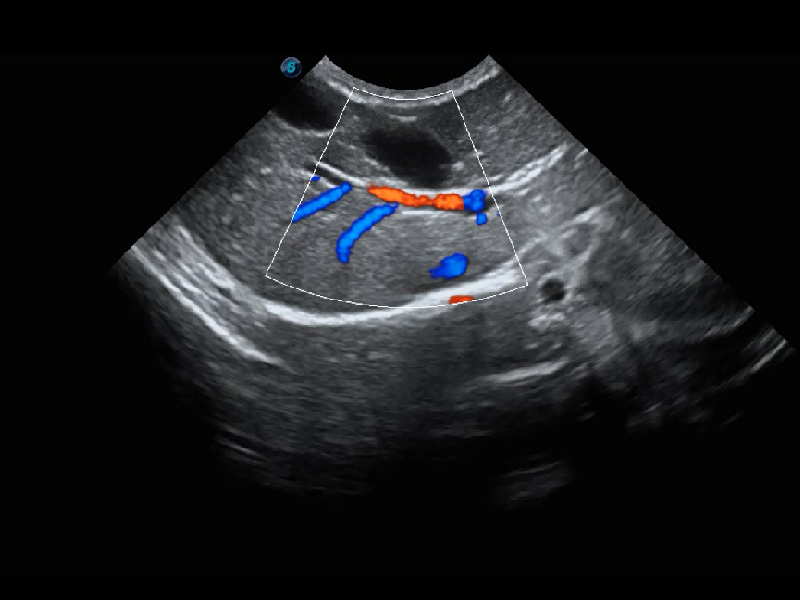

ProPet 60 作为一款高端台式动物超声设备,为动物医生的日常诊断提供了一系列贴合动物临床需求、解决临床实际问题的高级成像功能。凭借全系列高清探头,满足医生对腹部、心脏、生殖、浅表、肌骨等成像的所有需求,切实帮助您提升检查效率,提高诊断信心。

动物是人类最亲密的朋友和最值得信赖的伙伴。竞技宝(JJB)官方网站也一直致力于探索动物专用的超声影像解决方案。 全新推出的ProPet系列,是竞技宝(JJB)官方网站在动物超声影像智能化、专业化、精准化的一次跨越式革新。动物不能用言语来表述自己的不适,通过超声影像,ProPet系列搭建了动物医生与不同物种沟通的“桥梁”,为动物医生注入了“治愈之力”。